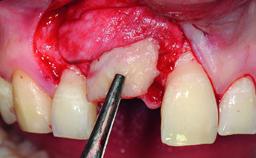

A healthy 37-year-old female patient was referred for a consultation on the replacement of missing tooth 21 with an implant-supported restoration. She stated that several years previously the tooth had been traumatically avulsed following a motor vehicle accident. The tooth was replaced with a three-unit fixed partial denture (FPD) immediately afterwards. Over time, she became disillusioned with the FPD and looked for a different option, including orthodontic therapy. She presented still in her orthodontic appliances, with the pontic sectioned free from the FPD but attached to the archwire. Her orthodontist felt that orthodontic treatment had been successfully completed, but nevertheless referred her before removing the appliances in case adjustments were necessary.

| Bone Augmentation | Horizontal|Simultaneous |

| Augmentation Materials | Xenogenous|Membrane |

| Soft Tissue Grafting | Simultaneous |

| Bone Volume | Deficient horizontally, allowing simultaneous augumentation |